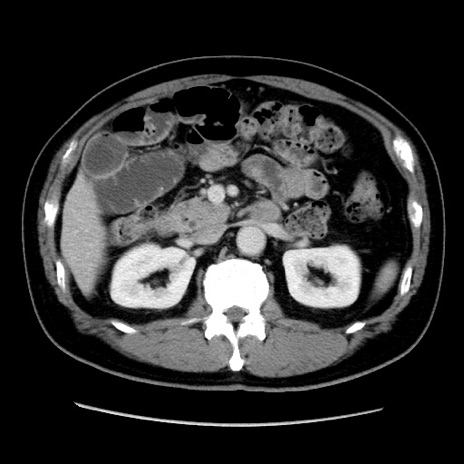

症例16(横断像)

【症例】 70歳代男性

【主訴】 腹痛、嘔吐

【現病歴】 約1ヶ月前より間欠的に腹痛と嘔吐あり、当院消化器内科を受診したところCTで多発する肝臓のLDAを指摘され、精査中であった。以降は消化器症状は安定していたが、2日前より嘔気と腹痛があり、同日より排便・排ガスが消失した。改善認めず、 本日、救急外来を受診した。

【既往歴】 大腸ポリープ切除後。

【身体所見】意識清明・会話良好、BT 36.3℃、BP 127/80mmHg、 P 80bpm、腹部:膨満あり、平坦・軟、上腹部正中および下腹部正中に圧痛あり、反跳痛なし、筋性防御なし。

【データ】WBC 7200、CRP 0.77